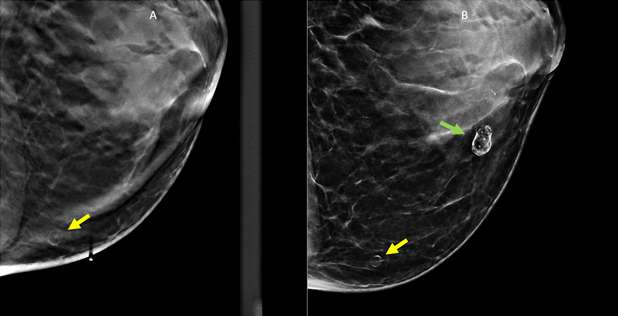

Case: Fat Necrosis of Breast Figure 3

Figure 3: 37 year old female with history of prior breast implant removal and fat grafting, presenting with palpable lumps. Left CC mammographic views. (A) Initial mammogram shows subtle rim calcified oval mass (yellow arrow). (B) Subsequent follow-up one year later shows increased conspicuity of the far medial oval mass. A second more central rim calcified mass is also present (green arrow), also consistent with fat necrosis.